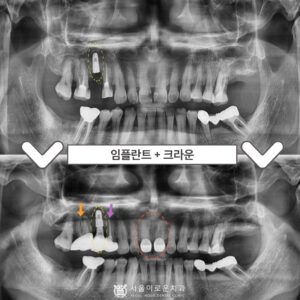

부천서울이로운치과 과거에 치료받았던 보철이 불편하다면? 안녕하세요! 부천서울이로운치과 대표원장 이경중입니다 🙂 앞니는 어금니와 달리 우리가 말할 때나 음식을 먹거나 미소를 지을 때 외부로 드러나 보이는 부분이기 때문에 심미적인 부분에서도 중요한 부분을 차지하게 되는데요. 그렇게 때문에 적절하지 못한 보철물로 인해 보기 좋지 않거나, 잇몸 건강에 문제가 있는 경우 재보철을 통해 더보기…